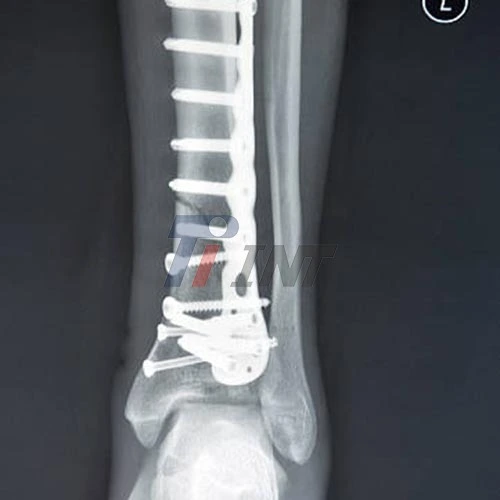

Are Titanium Leg Plates Safe for Long-Term Use?

Titanium leg plates have risen as a progressive arrangement in orthopedic surgery, advertising unparalleled benefits for long-term utilize. These inserts are without a doubt secure and profoundly successful for expanded periods, much appreciated to their uncommon biocompatibility, toughness, and resistance to erosion. Manufactured from high-grade titanium alloys like Ti6Al4V ELI, these plates are engineered to integrate seamlessly with the human body, minimizing risks of rejection or adverse reactions. Their lightweight however vigorous nature guarantees understanding consolation without compromising on quality, making them a perfect choice for long-term bone stabilization and bolster.

Durability and Strength: Built to Last

When it comes to long-term use, the durability of an implant is paramount. Titanium leg plates gloat a noteworthy strength-to-weight proportion, advertising strong bolster whereas remaining lightweight. This special combination permits the plates to withstand the day by day stresses and strains put on bones without including superfluous burden to the quiet.

The fatigue resistance of titanium is another critical factor contributing to its long-term safety. Unlike some materials that may weaken over time due to repeated stress, titanium maintains its structural integrity even under cyclic loading conditions. This strength guarantees that the leg plate proceeds to give steady bolster all through the mending prepare and past, diminishing the hazard of embed disappointment or the require for modification surgeries.